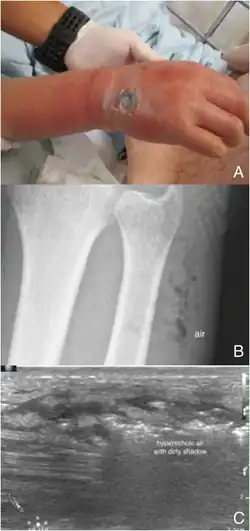

Point-of-care ultrasonography (POCUS)

Point-of-care ultrasound (POCUS) may be useful in the diagnosis of NF if MRI and CT are not available.[18] It can also help rule out diagnoses that mimic earlier stages of NF, including deep vein thrombosis (DVT), superficial abscesses, and venous stasis.[18] Linear probes are generally preferred for the assessment, especially in the extremities.[18]

Findings characteristic of NF include abnormal thickening, air, or fluid in the subcutaneous tissue.[18] This can be summarized as the mnemonic "STAFF" (Subcutaneous irregularity or Thickening, Air, and Fascial Fluid).[18] The official diagnosis of NF using ultrasound requires "the presence of BOTH diffuse subcutaneous thickening AND fascial fluid more than 2 mm."[18] Gas in the subcutaneous tissue may show "dirty acoustic shadowing."[15] However, similar to other imaging modalities, the absence of subcutaneous free air does not definitively rule out a diagnosis of NF, because this is a finding that often emerges later in the disease process.[18]

Plain radiography (X-ray)

It is difficult to distinguish NF from cellulitis in earlier stages of the disease using plain radiography.[15] X-rays can detect subcutaneous emphysema (gas in the subcutaneous tissue), which is strongly suggestive of necrotizing changes. However, air is often a late-stage finding, and not all necrotizing skin infections create subcutaneous emphysema. Hence, radiography is not recommended for the initial diagnosis of NF.[15] However, it may be able to identify the source of infection, such as foreign bodies or fractures, and thus aid in subsequent treatment.[15]